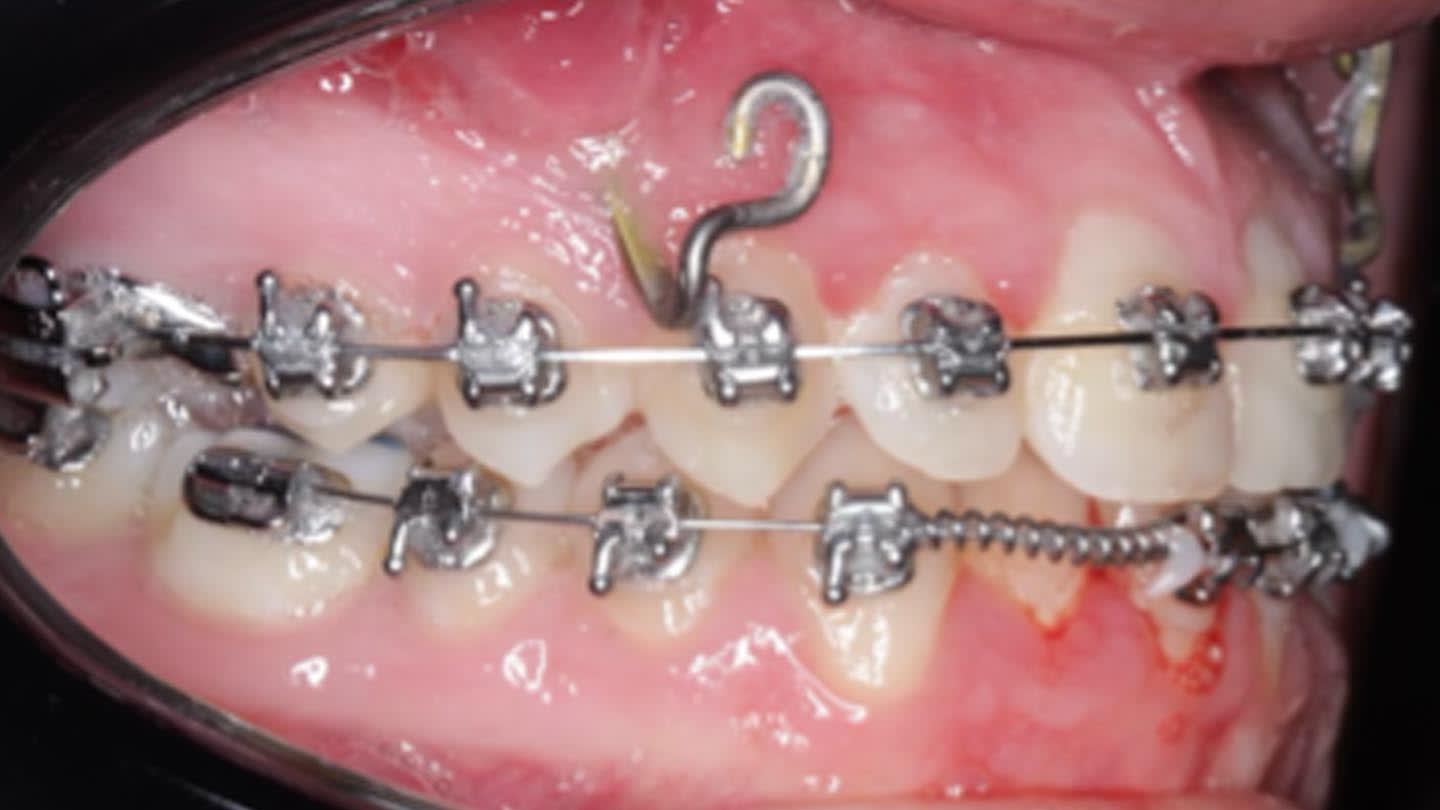

Despite variability in appliance design, all studies reported favorable outcomes with skeletal expanders for addressing transverse deficiencies in young adults. A case presentation illustrating treatment in a 16-year-old patient is shown in Figure 2 through Figure 39. (An additional case presentation may be viewed at compendiumlive.com/go/cced2110.) The studies also agree on the importance of individualizing miniscrew length and diameter in each case.25,26,30-32,34